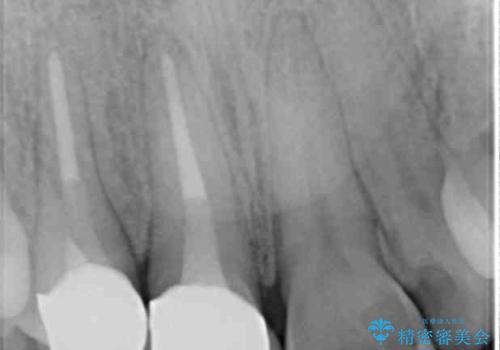

小臼歯の歯根長が長いことを治療前にレントゲンで確認し抜歯部位を決定しました。

犬歯は歯根が長く寿命も長い歯で、咀嚼機能時も重要な役目を果たすため、基本的に矯正の便宜抜歯に選択する歯ではありません。(一般的には第一小臼歯もしくは第二小臼歯が選択されることが多いです)

本症例では、様々な抜歯パターンの3Dシミュレーションを行い患者様と相談を重ねリスクをご理解頂いた上で、患者様のご希望により例外的に犬歯の抜歯を行いました。

側方運動時に大きな役割をもつ犬歯がないため、今後の定期健診で歯の状態を注意深く観察していく必要があります。